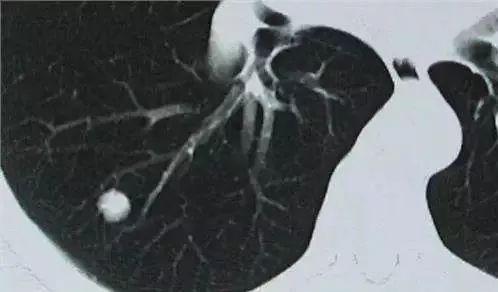

今年56岁的张先生,烟龄20多年,五年前因为住院手术,查过一次肺部CT,提示肺部“结节”,建议定期复查。五年来,张先生并没有按照医生的嘱咐定期复查。平时除了早上偶尔有痰,感冒后有点咳嗽外,没有其他明显的症状。最近因为一个亲戚查出癌症,家人劝张先生做个体检,结果发现他肺部的“结节”增大了,进一步检查怀疑是肺癌,最后做了手术。很多肺癌的患者就是这样,他们几乎没有任何特别的症状,只是在体检中发现结节,然后诊断肺癌的。今天,龙医生就来科普一下肺部“结节”的问题。

肺癌普查的主要手段美国国家癌症中心,建议对年龄在55~70岁、每年吸烟超过30包的高危人群,进行低辐射剂量的肺部螺旋CT检查,以筛查肺癌。这些人群中,往往能够发现一些明确的肺癌患者。但在检查过程中,也发现有一些人并没有明显的肺癌迹象,只查出了“孤立性”的肺结节。

什么是孤立性肺结节?孤立性的肺结节,是指被肺实质完全包围的单发小病灶,直径通常≤3cm,边界通常是清楚的。这些患者通常无症状,也没有伴随肺门淋巴结肿大、肺不张和胸腔积液等表现。对人群的肺癌筛查研究报告显示,有恶性肿瘤发生高风险的吸烟者,孤立性肺结节的患病率高达50?还有其他的一些流行病学调查显示,在肺部CT上偶然发现肺结节的发生率为30?右。放射学上,通常将测得的直径不超过3cm的病变称为结节,而大于3cm的则称为肿块,结节和肿块的区分很重要。